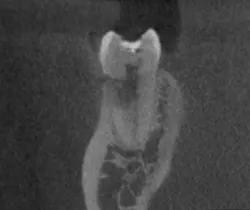

Top endodontics articles